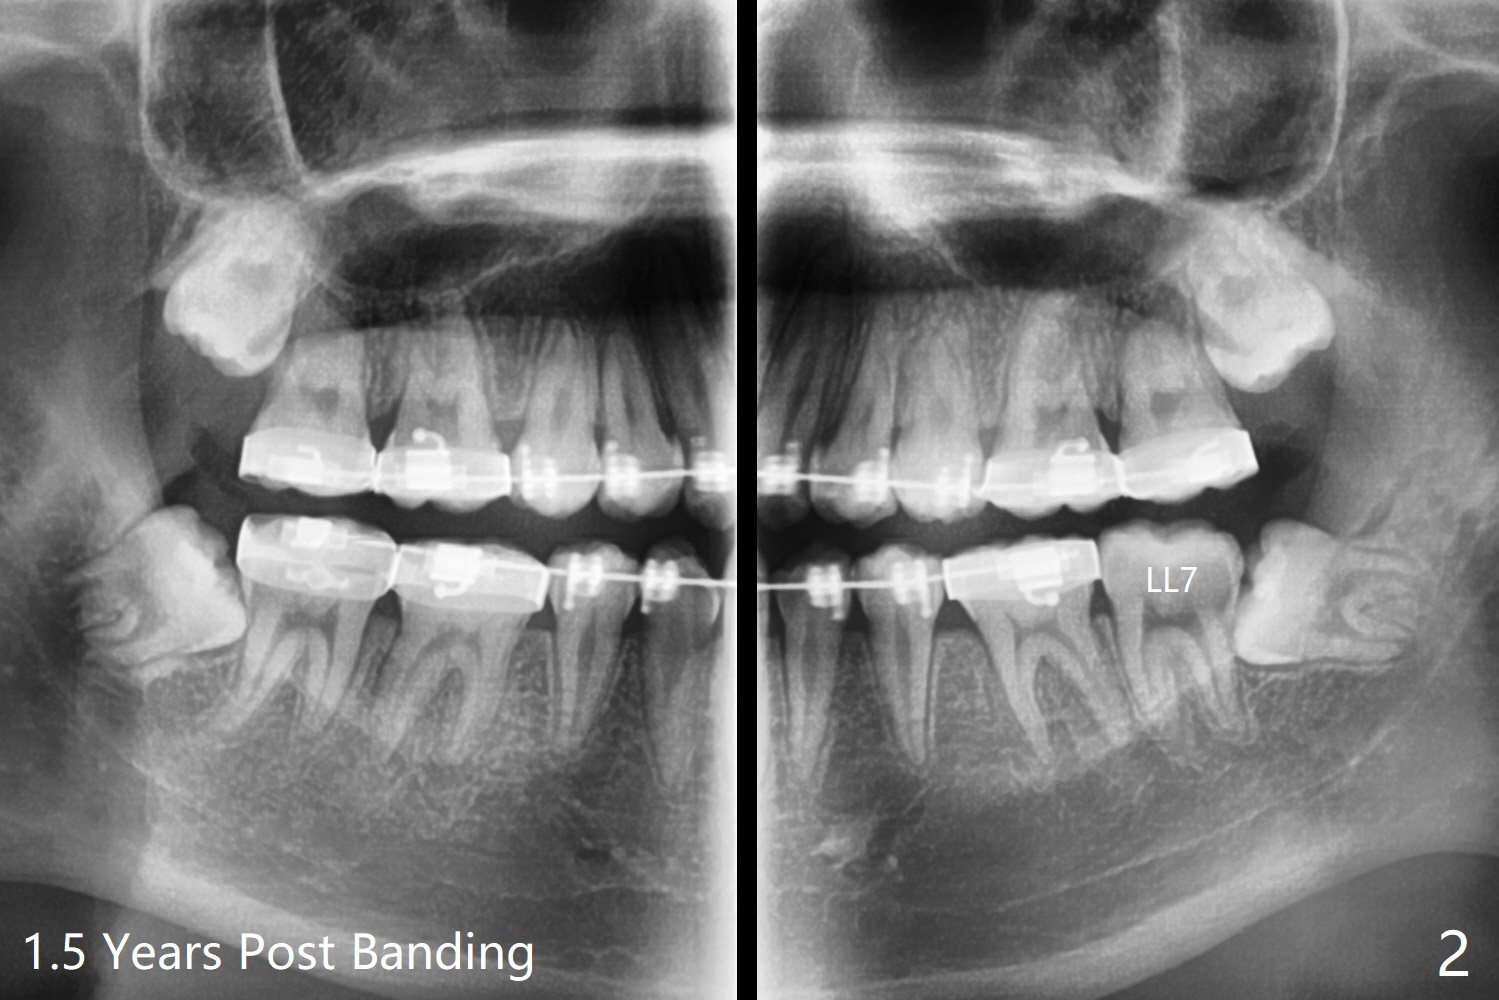

15岁男孩分离器使用后(图一:箭头)无法在左下7放置band,可能因为8阻生(图一,与图二对比)。1.5年后左下8萌出(图二),下颌8拔除,牙槽窝放置Osteogen Plug(图三),八个月后牙槽窝愈合(图四)。